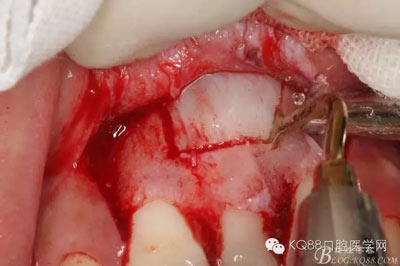

圖13.超聲骨刀清理周圍組織,21有Ⅰ°松動

圖14.牙冠周圍滲血多,無法粘結(jié)托槽。位置也高,隨與家屬溝通,暫時保留乳Ⅰ。待21初步穩(wěn)定,再考慮正畸牽引

圖15.輕輕的把21牙冠牽引至乳Ⅰ根尖方向,并擺正牙冠位置。(拔苗助長)